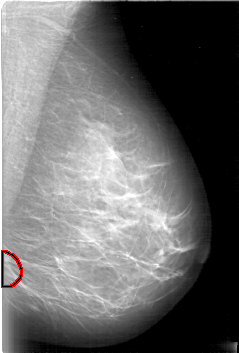

D_4006_1.LEFT_CC

FILE: D_4006_1.LEFT_CC.OVERLAY

TOTAL_ABNORMALITIES 1

ABNORMALITY 1

LESION_TYPE MASS SHAPE OVAL MARGINS OBSCURED

ASSESSMENT 0

SUBTLETY 5

PATHOLOGY BENIGN

TOTAL_OUTLINES 1

BOUNDARY